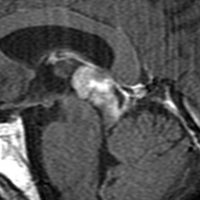

左はT2強調画像,右はFLAIR画像です。中脳視蓋 tectum の中でも上丘が腫瘍化していることが解りますし,松果体は正常の大きさで腫瘍の上に乗っていますから,松果体腫瘍ではないことが解ります。上髄帆にも浸潤しています。